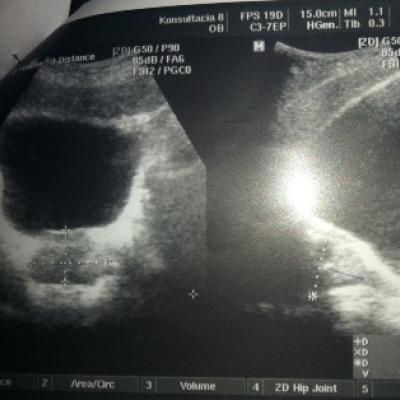

Добрый день! Дайте совет пожалуйста! Мне 30 лет. В декабре 2010 г. обнаружен хронический простатит, сделана узи, назначено лечение :

Псоле второго раза было сделано УЗИ, обнаружено образование камней.